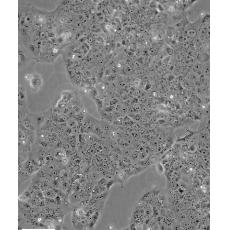

JEG-3

中文名稱 人絨毛膜癌細胞

組織來源 妊娠性絨毛膜癌;腦轉移;女性

生長特性 adherent

形態特征 epithelial